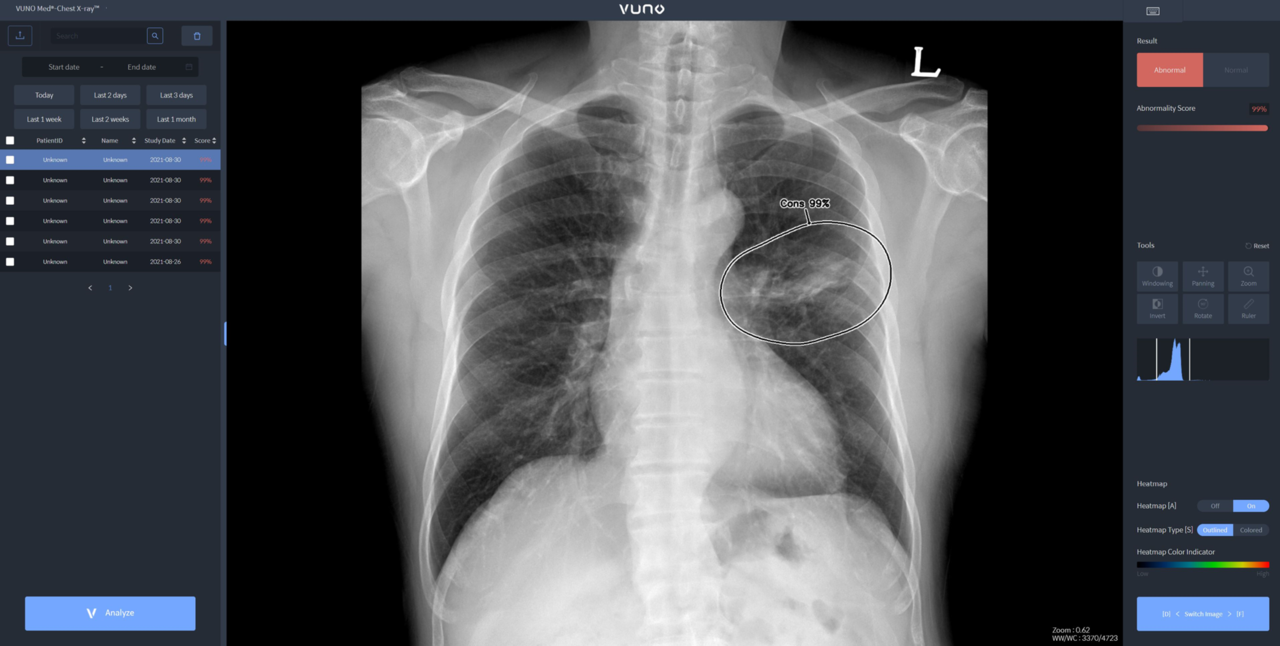

뷰노메드 체스트 X-레이는 흉부 X-레이 영상에서 결절, 경화, 간질성 음영, 흉수, 기흉 등 주요 이상소견을 높은 정확도로 탐지하는 AI 솔루션이다. 의료진에게 이상소견의 소견명과 위치를 제시해 결핵, 폐렴 등 주요 폐 질환 진단을 돕는다. 경량화 모델로 개발해 다양한 X-레이 장비에 쉽게 연동이 가능하다.